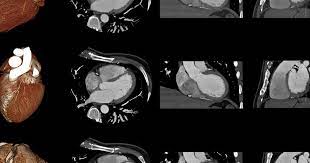

El término médico para esto es infarto de miocardio. El infarto agudo de miocardio («agudo» significa 'súbito', mio 'músculo' y cardio 'corazón'), frecuentemente abreviado como iam o ima, y conocido en el lenguaje coloquial como paro cardiaco, ataque cardiaco o infarto, refleja la muerte de células cardíacas provocada por la isquemia resultante del desequilibrio entre la demanda y el aporte de riego sanguíneo por la. Náuseas (ganas de vomitar), vómito, aturdimiento leve o mareo súbito, y sudor frío. Debe sospecharse una disfunción del ventrículo derecho en todo paciente con infarto de miocardio inferoposterior y aumento de la presión en la vena yugular asociados con hipotensión arterial o shock. Dolor, presión u opresión en el pecho, o una sensación opresiva o de dolor en el centro del pecho. O enfarte agudo do miocárdio, vulgarmente conhecido como ataque cardíaco, ocorre quando uma das artérias do coração fica obstruída por um coágulo, o que faz com que uma parte do músculo cardíaco deixe de funcionar por falta de oxigénio e nutrientes. Las arterias coronarias llevan sangre y oxígeno al corazón. El infarto de miocardio es una patología que se caracteriza por la muerte de una porción del músculo cardíaco que se produce cuando se obstruye completamente una arteria coronaria. Aunque los síntomas más frecuentes de un infarto son el dolor en el pecho, un síntoma común con la angina de pecho, y disnea o fatiga unos días antes, puede que no siempre se manifiesten de esta manera. Los síntomas del paro cardíaco repentino son inmediatos y drásticos, entre ellos: Llama al 911 o busca ayuda médica de emergencia si crees que estás teniendo un ataque cardíaco. Con infarto cardiaco, più precisamente infarto miocardico acuto (ima), spesso chiamato semplicemente infarto, si indica la necrosi (morte) dei miociti (le cellule del miocardio, il muscolo cardiaco) provocata da ischemia (mancanza di irrorazione sanguigna) prolungata, susseguente ad inadeguata perfusione del miocardio per squilibrio fra richiesta e offerta di ossigeno, spesso causata. Causas, tratamiento y cómo prevenir un infarto agudo de miocardio.